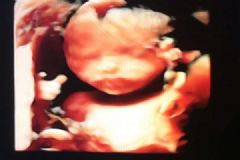

16日一早,李峰手机里“洛阳稀有血型之家”的信息再次响了起来,这次是一个喜讯。李峰献血拯救的待产孕妇顺利地诞下了一对双胞胎姐妹,目前母子平安。洛阳血站负责人李冬说,当时孕妇已经临产,考虑到是双胞胎,生育的时候有一定危险性,随时需要大量的稀有血应急,医院方面向血站求助。微信中的消息发出没多久,就有三名志愿者第一时间到现场献血,外卖骑手李峰就是其中之一。

李峰自2016年加入外卖骑手的大集体,经常在工作之余听说模范骑手那些感人的善举,有些事情虽然很小,但非常温暖。“这些都鼓舞我在别人需要帮助的时候,很自然地就会选择站出来,哪怕有时候会牺牲自己的利益。”事后,李峰得知自己捐赠的血液用来帮助一名待产的孕妇,还生了一对双胞胎姐妹,他特别开心。他看着一对小机灵的照片说:“等于一下子帮助了三个人,这别提有多高兴了,就比送100单外卖都开心”。